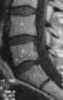

Endplate infarction